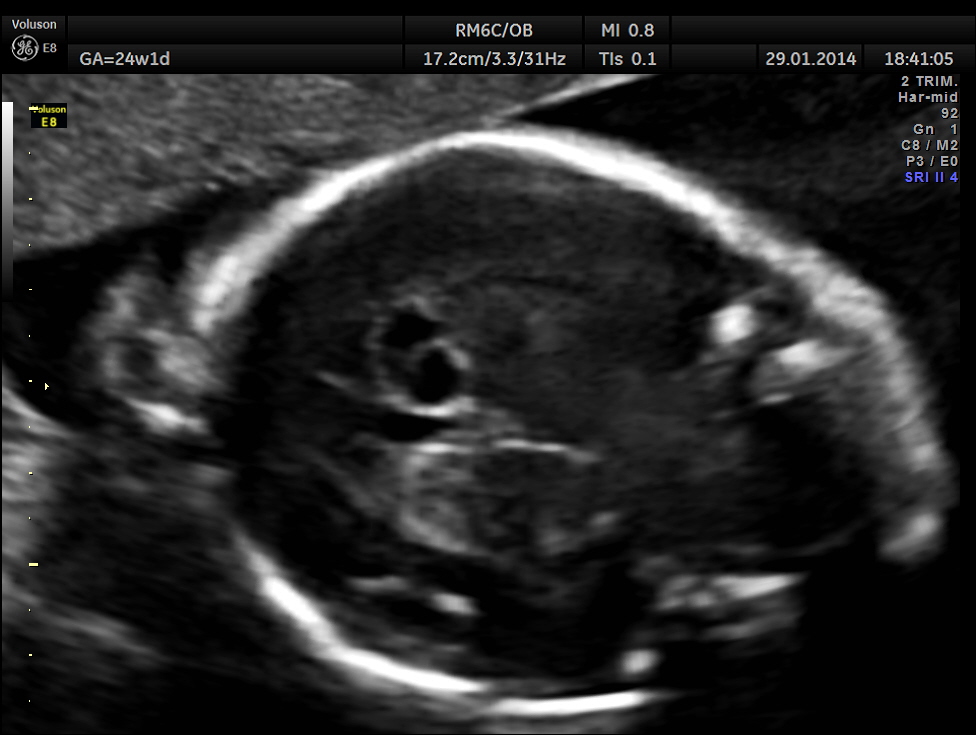

This was a 32-year-old lady – primi gravida . She was referred for an anomaly scan around 24 weeks gestation.Her earlier scan done in the first trimester elsewhere was reported as normal.

The following images were obtained. Unilateral choroid plexus cyst was seen .

Images of the other organs are given below.